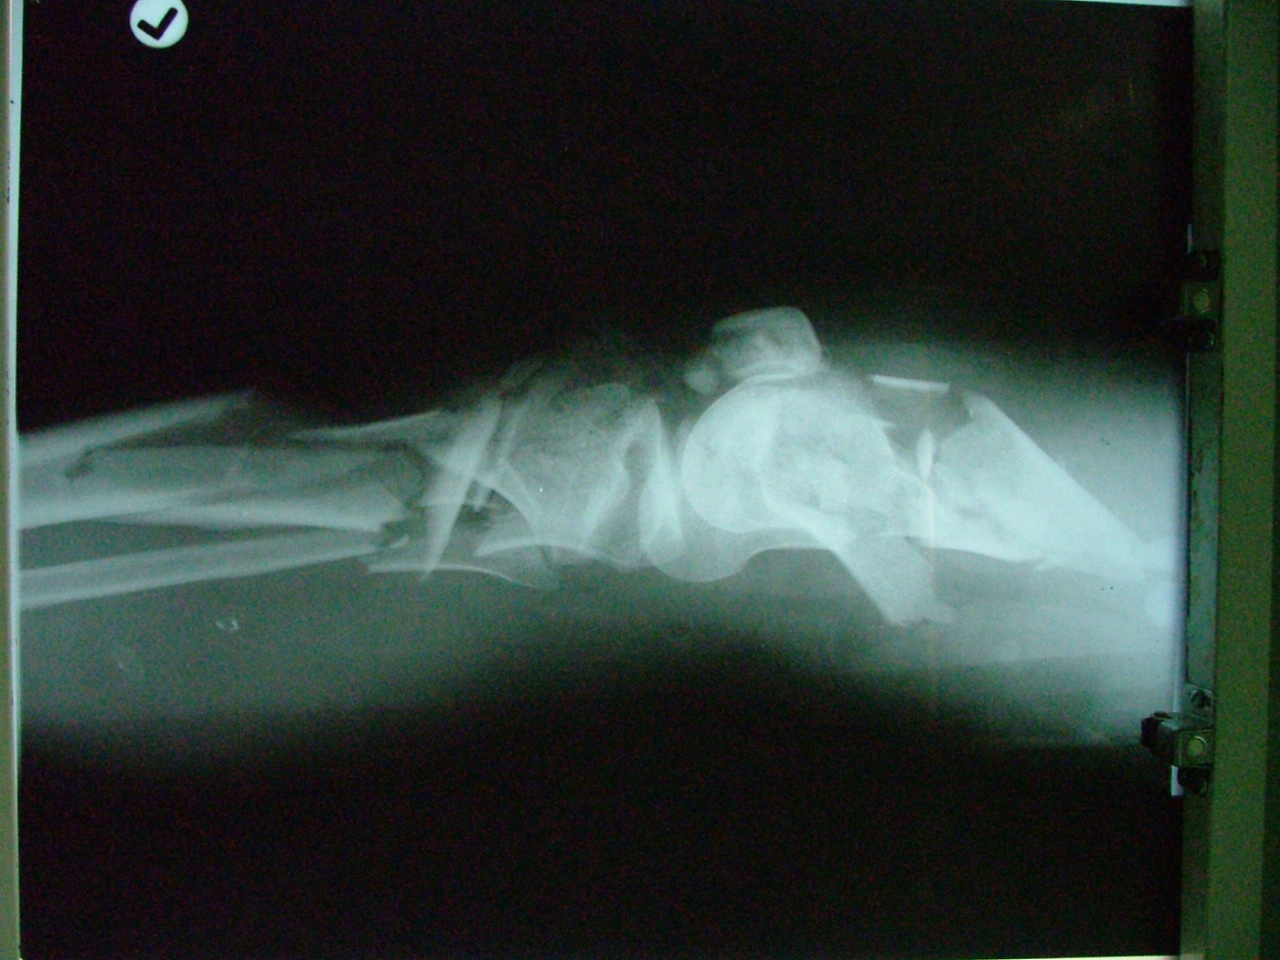

تهیه و تامین تجهیزات ارتوپدی و مشارکت در انجام اعمال جراحی ارتوپدی و عمل‌های نادر عضو تیم جراحی افزایش قد -جهت ترمیم شکستگی های قدیمی و جوش نخورده گی ها -طویل کردن اندامها- طویل کردن انگشت قطع شده - تعویض مفصل لگن _تعویض مفصل زانو _ بازسازی رباطACLوPCL_اصلاح ناهنجاریهای مادر زادی -با همکاری پزشکان و متخصصان مجرب آموزش دیده در روسیه و اتریش و سوئیس بروش جراحی ایلیزاروف و lon و lsa و واگنر و اسلایدینگ نیز جدید ترین روش افزایش قد و اندام در سال 1397 بنام hil هیل برای اولین بار- افزایش قد به 6 روش جراحی و جدیدترین روش در اروپا و روسیه. آدرس مطب _تهرانسر بلوار اصلی مجتمع سهند طبقه4 واحد 410